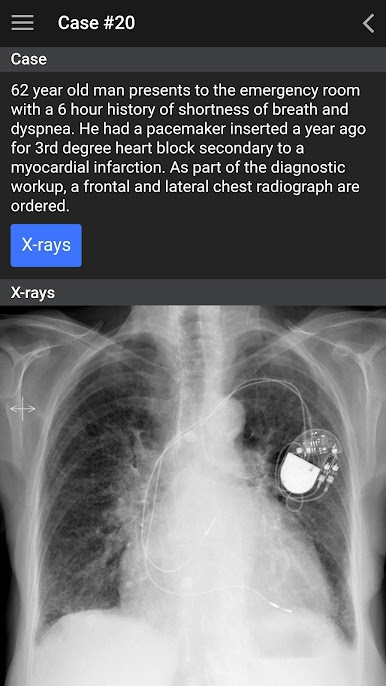

Diese App ist für die medizinische Auszubildende und medizinisches Fachpersonal entwickelt, das Vertrauen bei der Identifizierung von normalen anatomischen Strukturen zu erhöhen, die am besten geeignete Bildgebung Test Bestellung und gemeinsame Pathologie zu identifizieren.

Diese App ist an der University of British Columbia (UBC) auf der Radiologie Bachelor-Lehrplan, der in Vancouver, British Columbia, Kanada befindet. Die App-Inhalte in die organisierte vorklinischen (MS1, MS2) und klinischen (MS3, MS4, intern) Jahre. Der Fokus der vorklinischen Jahren ist auf normale Anatomie zu identifizieren und grundlegende Ultraschall Fähigkeiten zu erwerben und der Fokus der klinischen Jahren ist bekannt geworden mit Angemessenheit Kriterien Bestellung und Schlüssel Pathologie zu erkennen. Die Liste der klinischen Fälle in dieser App präsentiert werden aus dem Referendariat dritten Jahr Medizinstudent UBC entwickelte klinische Ziele "Must See".